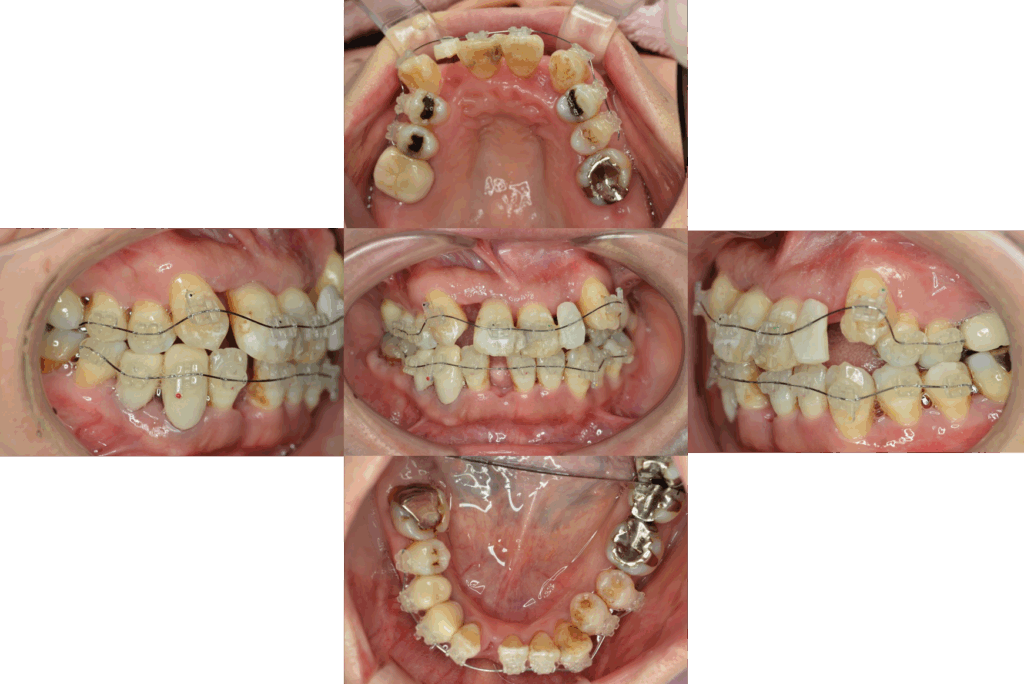

歯周再生療法 精密根管治療 歯周矯正治療 ジルコニアセラミック治療

Before

矯正治療

After

治療期間・回数

約3年・約20回

費用

1,400,000円(歯周矯正治療も含む)

治療のリスク

詰め物・被せ物の調整が難しく、割れた場合は再治療が必要。